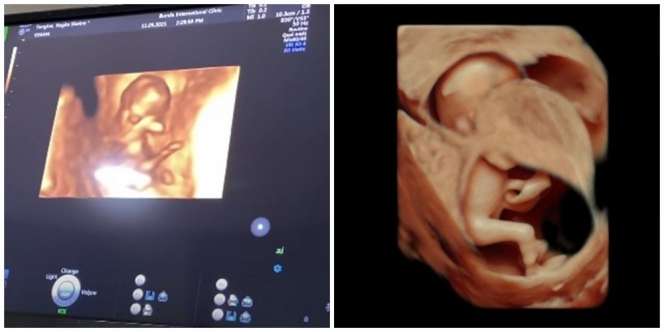

Dalam tayangan di kanal YouTube Rans Entertainment, Nagita Slavina membagikan momen saat dirinya melakukan cek USG 4D. Dengan teknologi tersebut, Gigi bisa melihat perkembangan janinnya lebih jelas.

Calon adik Rafathar itu terlihat aktif dalam pemeriksaan dokter. Sempat khawatir dengan keadaan calon anak keduanya, Gigi pun sekaligus berkonsultasi dengan dokter yang menangani.

Apalagi dengan potret sang bayi yang terlihat semakin jelas dalam pemeriksaan itu. Dokter pun menambahkan bahwa sang janin juga dalam kondisi normal. Banyak penggemar yang ikut merasa gemas nih dengan calon anak kedua Raffi dan Nagita. (YouTube/Rans Entertainment)